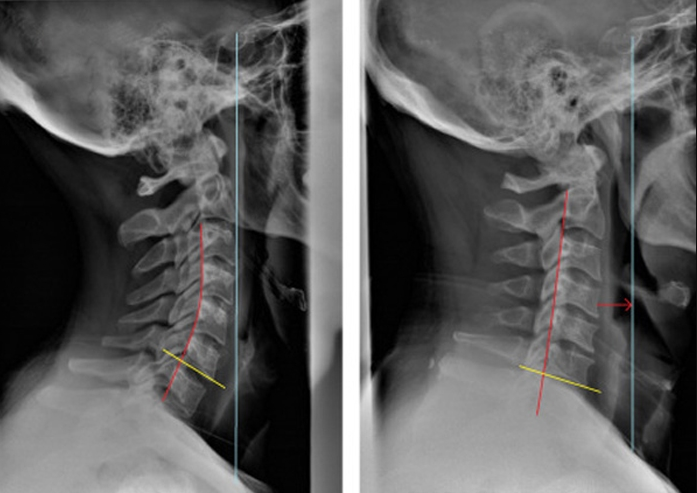

2.3 Đánh giá kết quả

Sau khi nhận kết quả, phim chụp x-quang phải đạt được những yêu cầu như sau:

- Lấy được toàn bộ đốt sống cổ.

- Thấy rõ đốt sống cổ và các khe khớp.

- Phim có độ nét tương phản. phim sạch không bị xước.